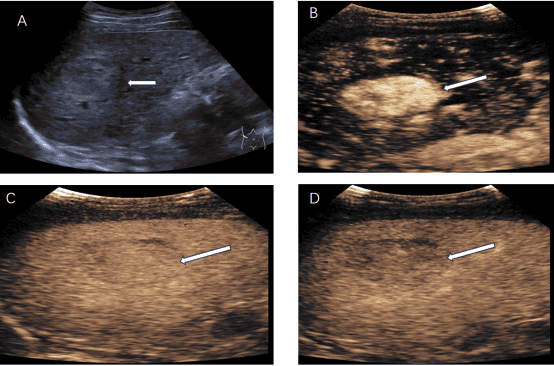

脏器静脉超声造影检查是在常规超声基础上,经静脉注射造影剂增强组织内微血管显示,实时动态观察正常组织与病变组织的血流灌注,以辅助疾病诊断及鉴别诊断。

该技术能清晰增强微血管显示,精准捕捉血流灌注差异,提升诊断与鉴别精度;可动态观察血流,助力明确病变边界、发现微小病灶;适用范围广,操作便捷、安全性高,为临床决策提供丰富血流动力学信息。